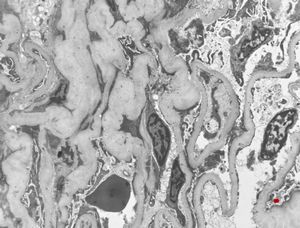

membranoproliferative glomerulonephritis

M,37y. | type I membranoproliferative glomerulonephritis (mesangiocapillary)